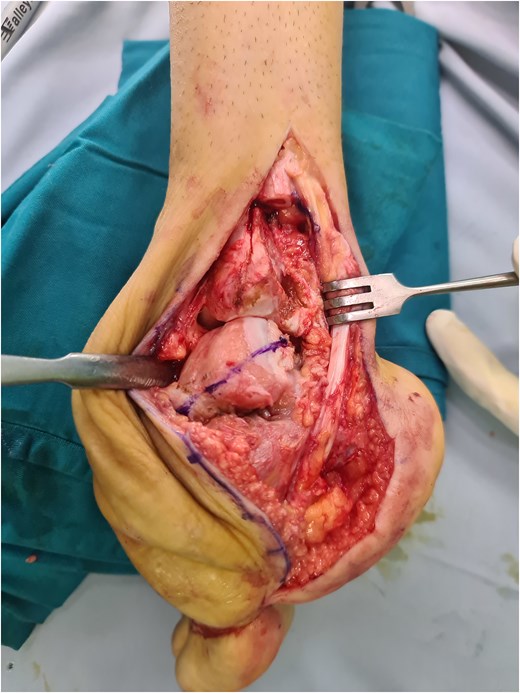

The patient was placed in the lateral decubitus position under regional anesthesia. The distal fibula was removed via the lateral transfibular approach. The plantar flexor tendon including the Achilles tendon was initially lengthened, but residual equinus remained due to bony obstruction as well as massive soft tissue contracture. Subsequent axial partial talectomy at the talar dome was performed as much as necessary to facilitate reduction. A lateral tibiotalocalcaneal plate that was applied to firm the ankle (Fig. 1d) was reinforced by a uniplanar external fixator (Fig. 1e and f). First metatarsal dorsal closing wedge osteotomy was completed to address the cavus midfoot. The surgical wound was irrigated and closed in a standard fashion.

(a) Preoperative clinical images; (b) and (c) preoperative radiograph; (d) intraoperative image after partial talectomy followed by (e) fixation with plate and screw; (f) immediate postoperative image depicting additional fixation with Schanz screw; (g) clinical images at 2 months postoperative (h) 2 months postoperative radiograph; (i) latest clinical images after 1 year postoperative; (j) latest radiograph after 1 year postoperative showing healed arthrodesis.

The partial talectomy method used in this case series was performed by removing a portion of the talar dome in axial plane using an oscillating saw to correct the hindfoot equinovarus deformity, mainly the equinus (Fig. 4). The bone cuts were done as much as necessary until the desired reduction was achieved. The lateral transfibular approach was selected due to its association with good exposure for deformity correction in the sagittal plane and its sufficient proximity to the articular surface. As mentioned before, bone cutting in this area will preserve the vascularization in the inferior talus or sinus tarsi, in contrast to the Lambrinudi procedure [11]. Compared with total talectomy, which results in an incongruous joint, partial talectomy is still able to facilitate proper contact between the distal tibia and cut talus. Various internal fixation methods are available to protect correction and to prevent recurrence. Generally, tibiotalocalcaneal fusion can be performed using multiple screws, plates and screws, or intramedullary nails. However, multiple screw placement would not be preferred due to poor bone stock. Gursu et al. reported the use of intramedullary nail fixation after talectomy in the management of severe rigid equinovarus deformity in adults. Intramedullary nails have a biomechanical superiority and ability to reduce incongruity between surfaces with sequential reaming [20]. Nevertheless, intramedullary nails are still not widely available worldwide, especially in developing countries, in which many similar neglected clubfoot cases can be found. Lateral plating is viable, especially when a lateral transfibular approach is used. Other than the anatomical tibiotalocalcaneal plate that is utilized in this study, various plates, such as reversed proximal humeral plates, can be applied as long as they enable sufficient screw placement [21].